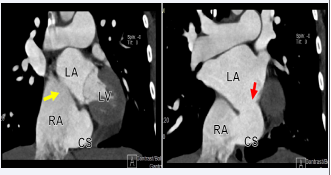

Patient was taken to the catheterization laboratory for ASD secundum type closure using Amplatzer device under TEE guidance. However, during procedure the multipurpose catheter crossed very inferiorly at the level of the coronary sinus (CS) into the LA. The left upper pulmonary vein identified very easily as well as a small CS vein, which is draining from the great cardiac vein. TEE showed that the multipurpose catheter in the LA, however, it did not go through the previously mentioned secundum ASD, raising the possibility of different co-existing septal defect. Procedure was aborted and patient was scheduled for CCTA to better define the septal defect and rule out the presence of PLSVC. CCTA showed a large ASD inferiorly, representing an UCS. The defect is large, measuring 24 mm in length, and both the superior and inferior vena cava are intact. The pulmonary veins drain in the LA. The right pulmonary veins emerge from a single trunk, while the left pulmonary veins emerge from a very short trunk that splits into two branches early on (Figures 6-9).

Cardiac computed tomography angiography (CCTA) in  sagittal displays showing dilated RA, ASD (Yellow Arrow), and  unroofed CS (Red arrow).

Figure 8: Cardiac computed tomography angiography (CCTA) in sagittal displays showing dilated RA, ASD (Yellow Arrow), and unroofed CS (Red arrow).